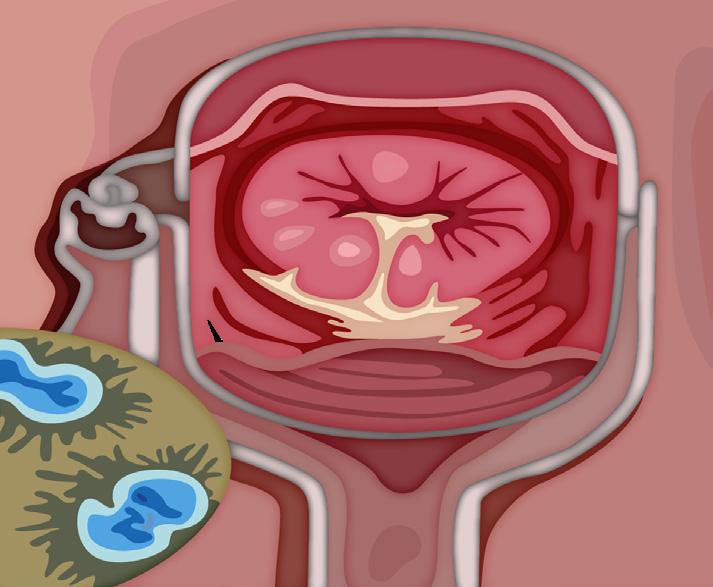

El flujo turbulento daña el endotelio de las válvulas activando la hemostasia y se forman vegetaciones asépticas formadas por plaquetas y fibrina (trombo estéril). Luego, estas se contaminan debido a una bacteriemia por un foco séptico, formándose una verruga bacteriana (vegetación séptica), la cual puede destruir la válvula (rotura de cuerdas tendinosas, músculo papilar) y formar abscesos, produciendo la clínica cardiaca; los émbolos sépticos que pasan a la circulación sistémica dan lugar a la clínica extracardiaca (en casos de ADVP, predominan los émbolos pulmonares).

Endocarditis no infecciosa como la Endocarditis de Libman-Sacks lupus eritematoso sistémico o síndrome antifosfolípido y la endocarditis marántica se asocia a estados de hipercoagulabilidad (cáncer, enfermedades autoinmunes, VIH)

La triada clínica es fiebre (95 %), soplo de regurgitación (85 %) y esplenomegalia (30 %) . Además, podría haber clínica extracardiaca producto de los émbolos sépticos al territorio de la arteria cerebral media, como hemiparesia por un ictus isquémico en pacientes jóvenes o manifestaciones embólicas pulmonares (tos, disnea y hemoptisis), que son más frecuentes en los pacientes ADVP.